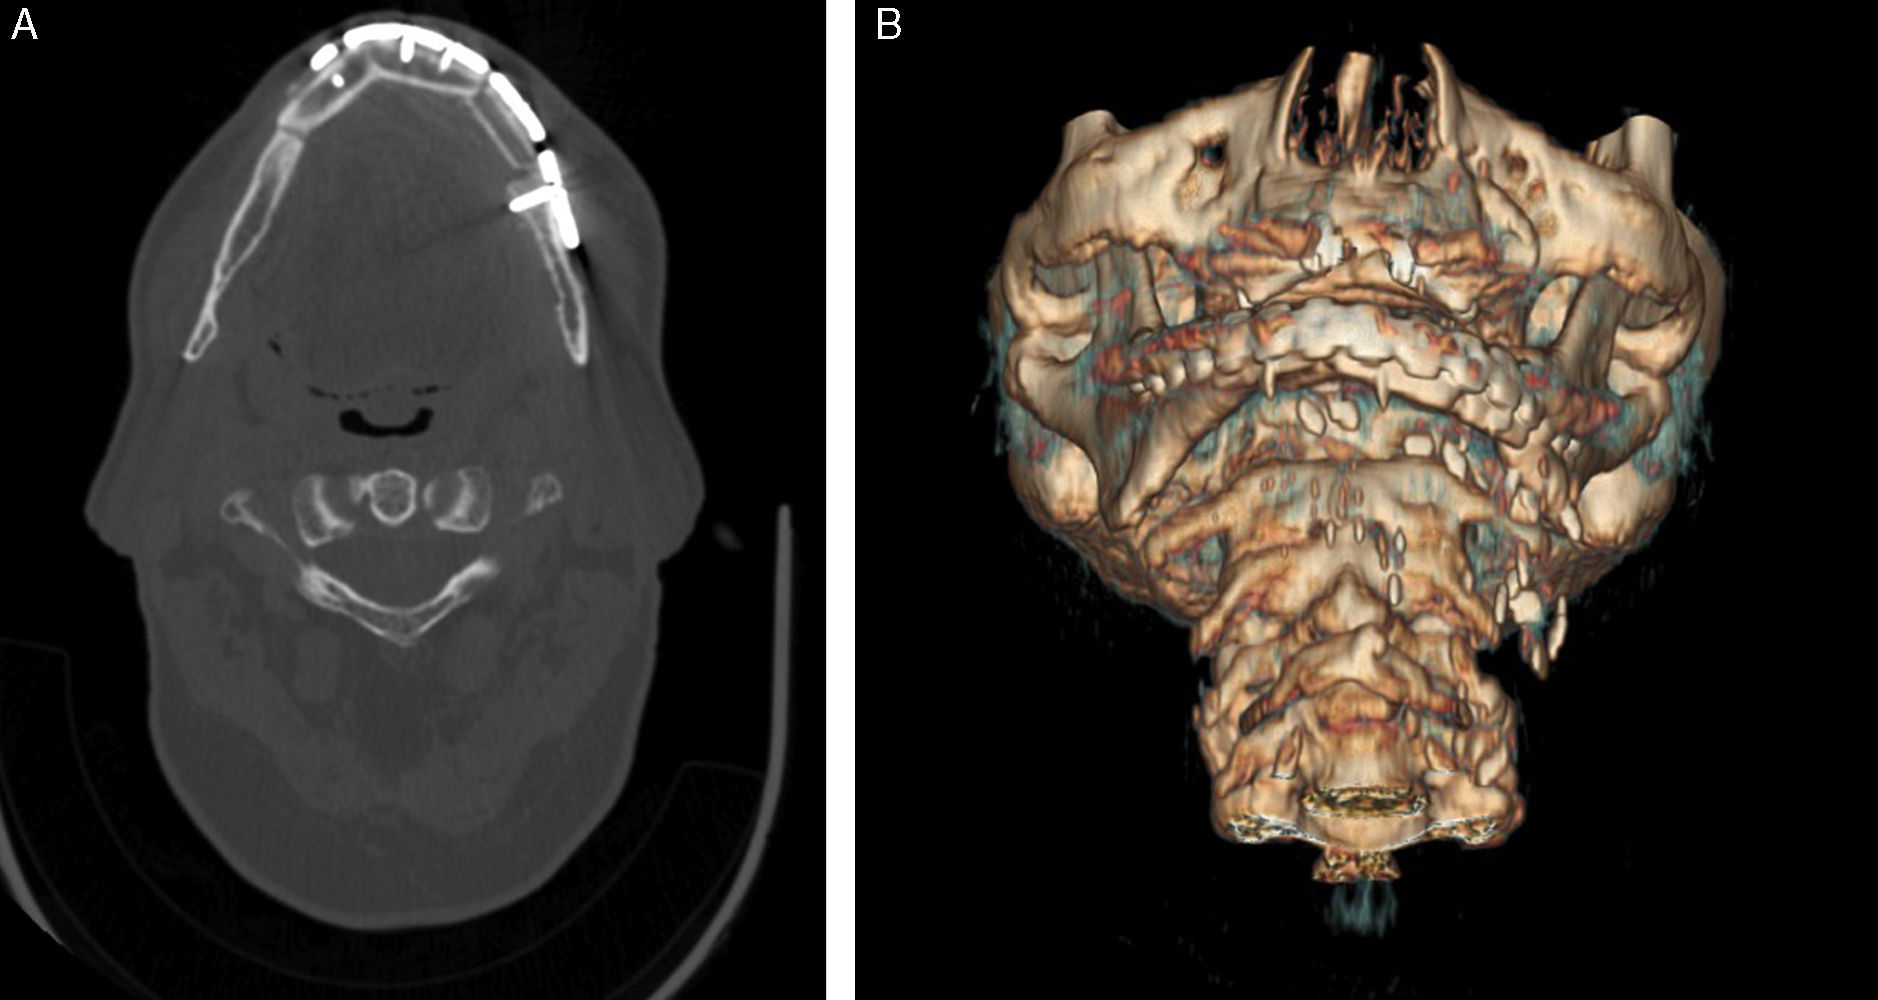

Caso clínicoPaciente varón de 70 años, que fue trasladado a urgencias bajo intubación orotraqueal por presentar traumatismo facial severo tras intento autolítico con arma de fuego. En la exploración física se objetivó una lesión traumática a nivel de tercios medio e inferior faciales, con pérdida de tejidos óseos y blandos (pérdida total de espesor completo del labio inferior, región perioral, mentoniana y pérdida parcial a nivel de labio superior). Se procedió a la realización de una tomografía computerizada (TC) craneofacial, que descartó daño cerebral y mostró una pérdida extensa de sustancia a nivel mandibular, con fracturas múltiples maxilares, fractura de suelos orbitarios, fractura de huesos propios y tabique nasal óseo (fig. 1). El paciente fue trasladado a quirófano, donde se realizó traqueostomía reglada, limpieza y hemostasia de heridas faciales y retirada de fragmentos óseos conminutos y cuerpos extraños. Seguidamente se realizó puenteo del defecto óseo mediante una placa de reconstrucción mandibular de 2,5mm y cierre primario de tejidos blados. Se comprobó la estabilidad de fracturas en tercio medio, por lo que se adoptó una actitud expectante. Se realizó reducción nasal cerrada (figs. 2 y 3). El paciente permaneció en la Unidad de Cuidados Intensivos durante cuatro días.

A) Aspecto inicial del paciente a su llegada a urgencias. Se observa el importante déficit de tejidos óseos y blandos en tercio facial inferior. B) Apariencia tras tratamiento quirúrgico inmediato (limpieza de heridas, hemostasia, puenteo del defecto óseo y cierre primario de partes blandas).